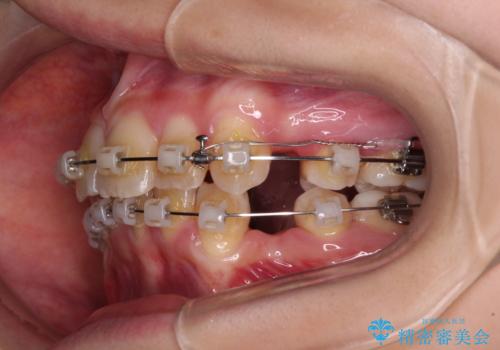

- クリアブラケット

- 2年9ヶ月

- 前方に飛び出した前歯と、下顎の八重歯を気にして来院された患者様です。

口元の突出感を改善するため、上下左右の第一小臼歯4本を抜歯し、ワイヤー装置にて矯正治療を行うこととしました。